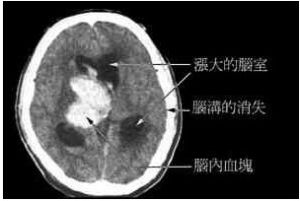

水腦症是指腦室積水。人腦的構造除了一般常聽說的血液循環外,還有所謂腦脊髓液的循環。腦脊髓液像血液循環一樣,在大腦構造內是流通的。這方面在大腦的詳細構造,有所謂的“腦室”或是“腦池”,就像是水庫或是池塘一樣的構造,在一般的電腦斷層上可以很清楚的看到。

腦水在這些池塘或水庫是流動的,腦水由腦中央的腦室,流過大腦的表面,以及腦池,然後在頭頂吸收。如果流通的路線被阻塞了,那么水庫或是腦池的水會漲大起來,腦壓會升高,腦會受到壓迫,人就會變得反應遲鈍。這就是所謂的水腦症。俗稱腦內積水。

水腦症 腦積水可能由腦脊液(CSF)流動削弱、再吸收削弱,或腦脊液產生過多引起。正常顱內壓是顱骨壓力與血壓、腦脊液和腦實質壓力之間的平衡(顱骨壓力=腦壓+腦脊液壓力+血壓)。